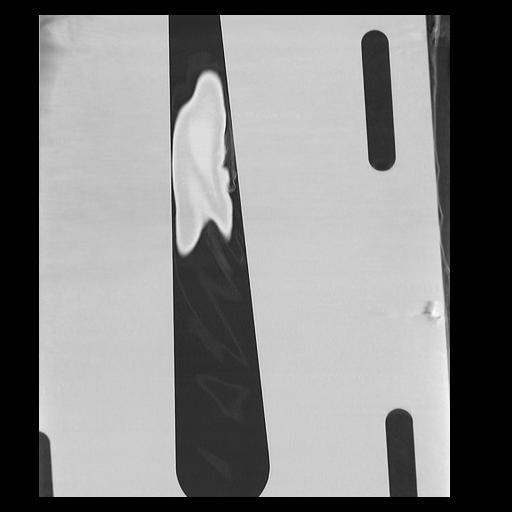

32 PULMON,CE,Coronal,3.000,PULMON,Coronal,